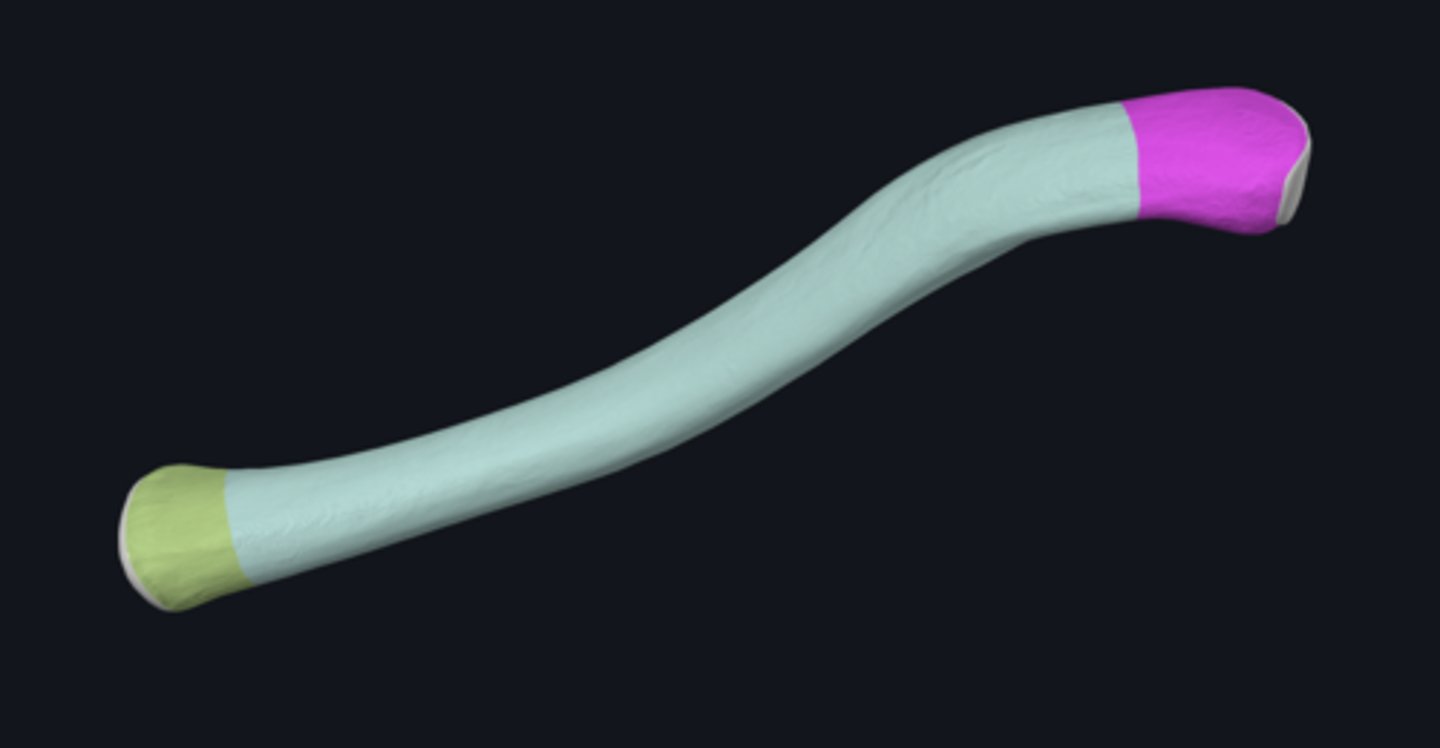

bones of the upper limb

anatomical neck of humerus

body of humerus

condyle of humerus

greater tubercle

head of humerus

lesser tubercle

anterior border of humerus

anterolateral surface of humerus

anteromedial surface of humerus

lateral border of humerus

lateral epicondyle of humerus

lateral supracondylar ridge

medial border of humerus

medial epicondyle of humerus

medial supracondylar ridge

posterior surface of humerus

Capitulum

coronoid fossa

Crest of greater tubercle

crest of lesser tubercle

deltoid tuberosity

groove for ulnar nerve

bicipital groove

olecranon fossa

radial fossa

radial groove

surgical neck of humerus

trochlea